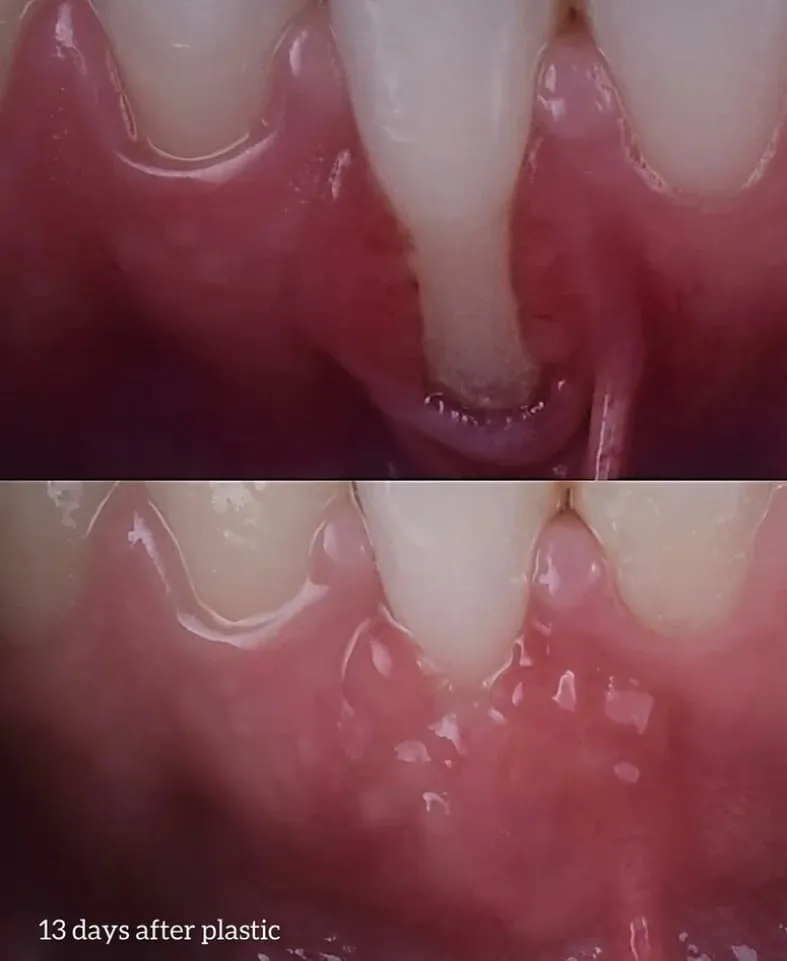

Gum plastic surgery